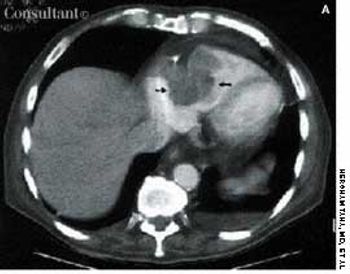

A 95-year-old woman was brought to the emergency department with hemoptysis. Erect posterior-anterior (A) and lateral (B) chest films showed a density at the base of the right lung posteriorly. A CT scan (C) revealed that the mass was the right kidney above the diaphragm and adjacent to the heart. The kidney had migrated through a foramen of Bochdalek.